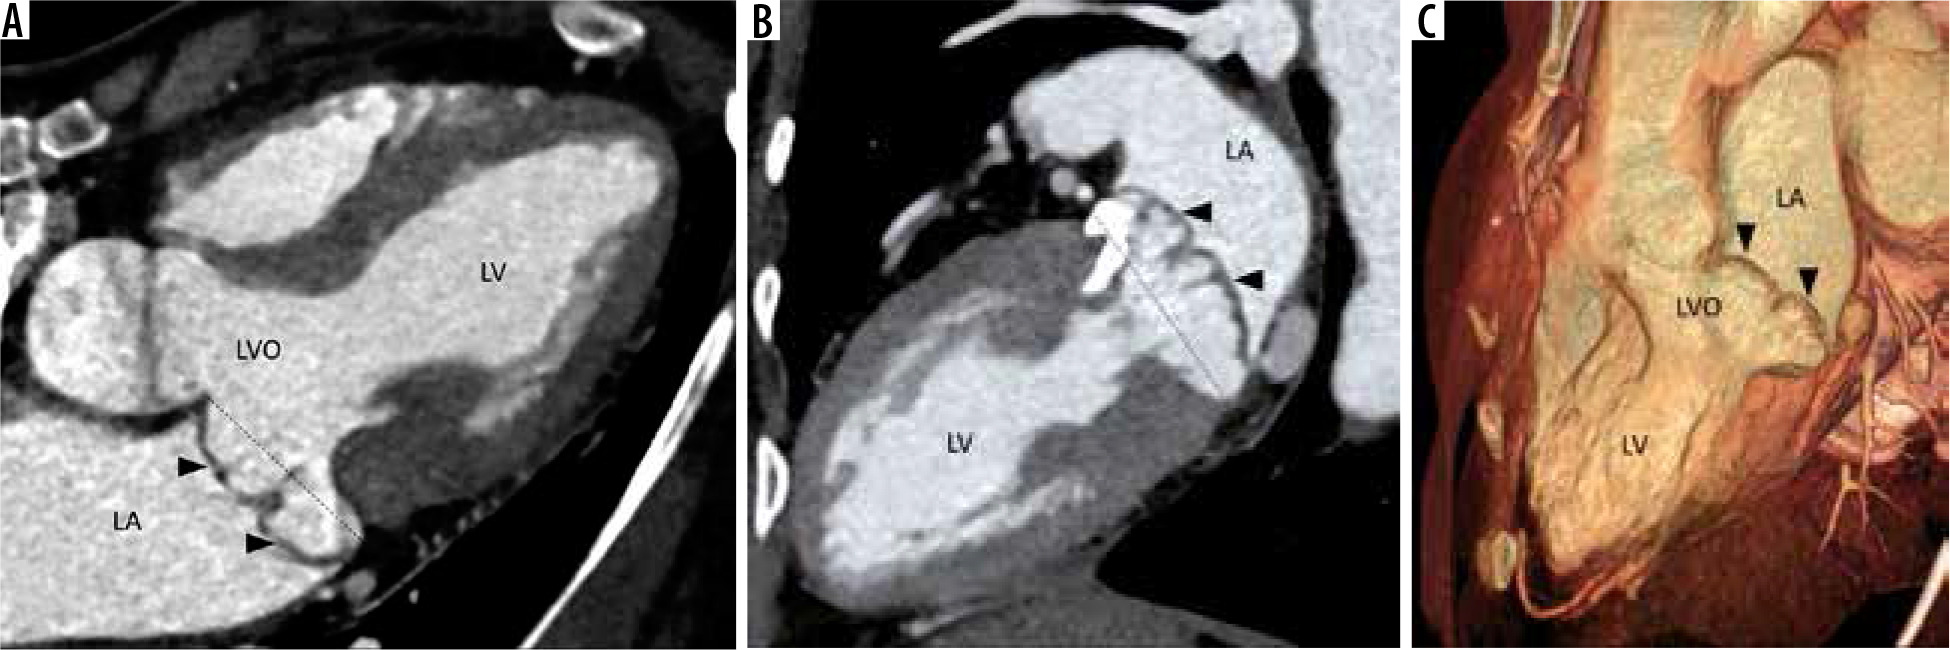

Figure 4

Multiplanar reconstructed image in the 4-chamber view (A), 2-chamber view (B), and volume-rendered image (C) demonstrate prolapse of both the anterior and posterior leaflets of the mitral valve (arrowheads) with resultant widening of the left ventricular outflow (LVO). Note is also made of calcification of the mitral valve annulus. LA – left atrium, LV – left ventricle